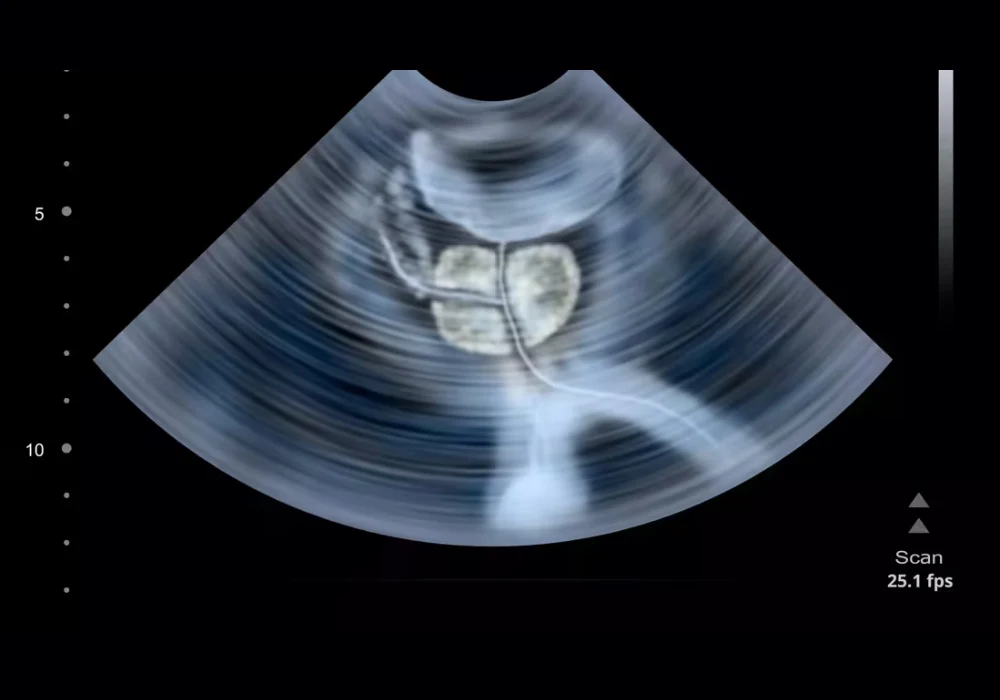

The AI model processes 3D mpUS acquired with automated protocols that combine conventional greyscale ultrasound, contrast enhancement and elastography. Patients with biopsy-proven disease who were scheduled for radical prostatectomy (RP) formed the positive reference set because whole-mount histopathology could map tumour extent. Men without csPCa were identified through low-suspicion magnetic resonance findings or negative systematic biopsies, creating a pragmatic control group aligned to real diagnostic pathways.

To approximate clinical behaviour, the outputs from the AI model were turned into simulated targeted biopsies. Heatmaps highlighting suspicious regions were used to select a small number of top-ranked targets per patient, reflecting how a proceduralist would prioritise sampling in a session with limited cores. A standard transperineal path was assumed to calculate whether a hypothetical needle pass would intersect a suspicious region. These steps provided a consistent patient-level framework without requiring live procedures, making it possible to compare internal and external results on a like-for-like basis.